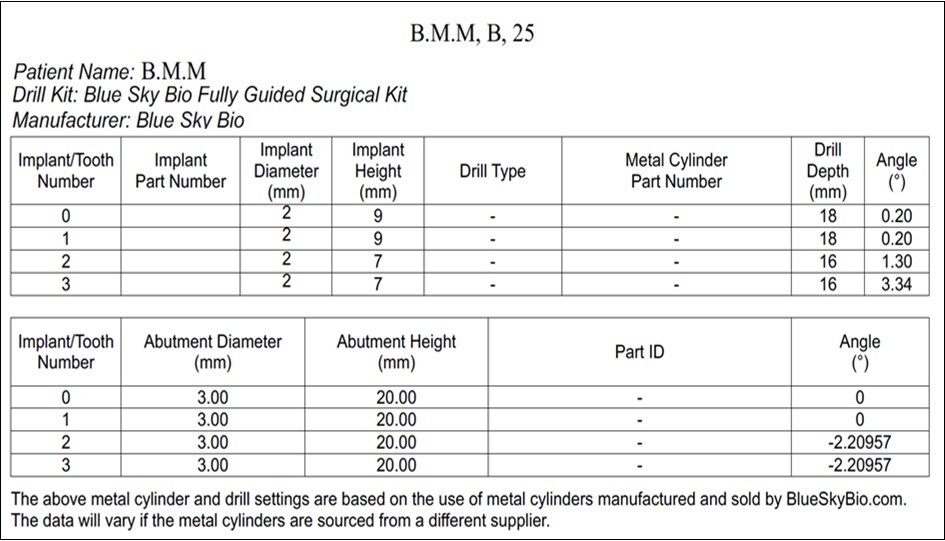

The most suitable antero-posterior mini-implant placement site is determined based on the width and thickness of the palatal vault. 4 self-drilling mini-implants (BENEfit®) were selected: 2 in the anterior palate (rugae area): 2.0 x 9 mm (ST-33-54209) and 2 in the posterior palate (para-midsagittal area): 2.0 x 7 mm (ST-33-54207). (Figure 2)

Figure 2.Mini-implant characteristics